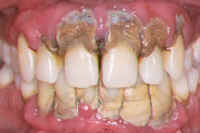

• Periodontitis: Advanced stage affecting supporting bone and tissues

If left untreated, gum disease can lead to damage of the supporting structures of the teeth and may eventually result in tooth loss. Early intervention helps in controlling the condition and maintaining overall oral health.